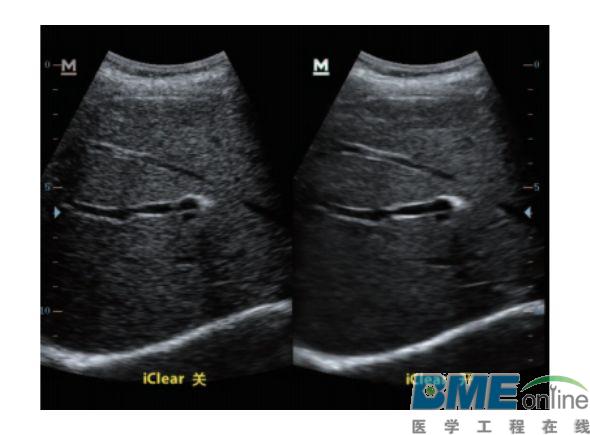

设备型号DP-50 全自动便携式超声诊断系统(迈瑞),该设备为DP 系列超声的较高级版本,具有iTouch 图像一键优化、 iBeam 复合成像、iClear 斑点噪声抑制、宽带频移谐波等技术。

iClear斑点噪声抑制: